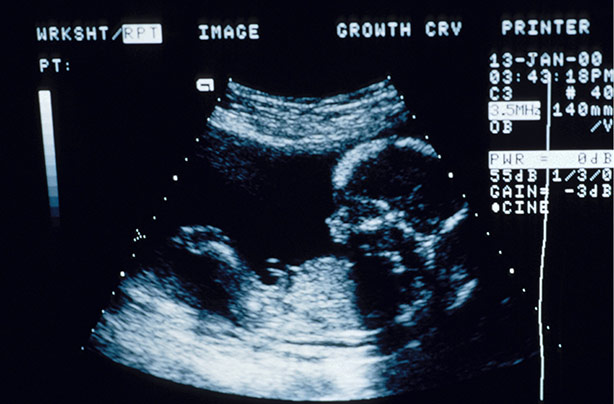

The skull theory is a fun gender prediction method, which some claim can determine if you're having a boy or girl from a 12-week ultrasound picture.

Also called the skull gender theory, it joins other techniques like the Nub Theory and ancient Chinese birth chart in trying to guess a baby's sex before the 20-week pregnancy scan. Similar to the Ramzi theory, the skull theory looks at ultrasound images of your baby in the womb, although the two look at different aspects of your baby's development.

Article continues belowUsing your 12-week scan photo, the skull theory looks at your baby's skull shape and size to predict the sex of your baby. But is this just another old wives' tale, or does the skull theory for gender really work? We'll take a look at the scientific evidence. Remember, this test is just for fun, like all baby gender predictor tests before the anatomy scan.

This means that it might be possible to work out whether a baby is male or female by studying the shape of their developing skull in a 12-week scan photo.

"This is sometimes seen on ultrasound, although the earlier the ultrasound is performed, the more limited views are," says Bastianelli. "The skull theory suggests assessing gender differences at around 12 weeks gestation. A fetal head at this age measures in circumference of around 80mm, which you can imagine is quite small to assess any minor visual differences in shape accurately."